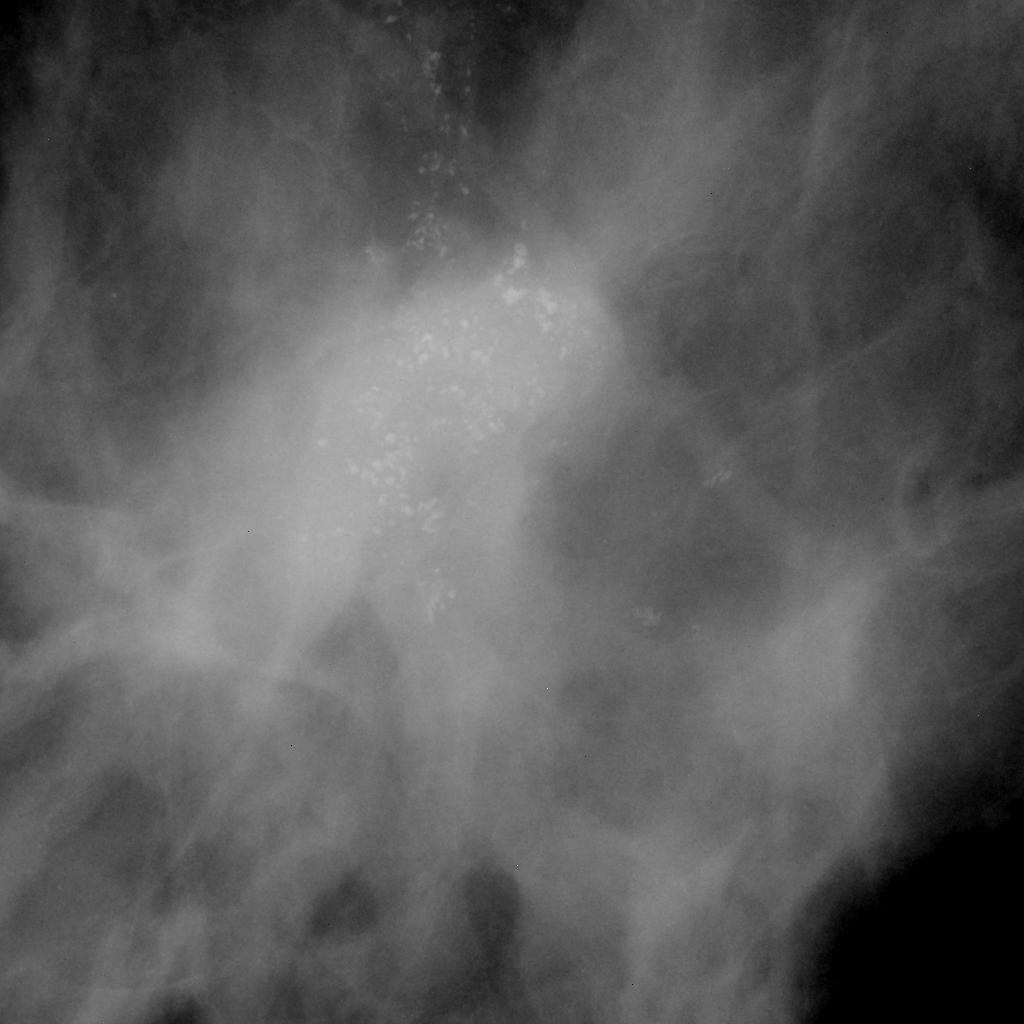

Spiculated Mass With Calcifications . For example, a spiculated (or stellate) lesion has a high positive predictive value for malignancy, often around 90% 2,. While they often represent a benign process, they can be a sign of cancer. This topic will review mammography technique, performance capabilities of mammography in particular patient groups,. Breast calcifications are calcium deposits found through screening mammograms. Masses with irregular shapes and indistinct or spiculated margins have a higher likelihood of malignancy. A) mammography of the left breast with mlo view demonstrates irregular, spiculated mass in the left breast at 12 o'clock (big white circle).

Masses with irregular shapes and indistinct or spiculated margins have a higher likelihood of malignancy. This topic will review mammography technique, performance capabilities of mammography in particular patient groups,. For example, a spiculated (or stellate) lesion has a high positive predictive value for malignancy, often around 90% 2,. While they often represent a benign process, they can be a sign of cancer. Breast calcifications are calcium deposits found through screening mammograms. A) mammography of the left breast with mlo view demonstrates irregular, spiculated mass in the left breast at 12 o'clock (big white circle).